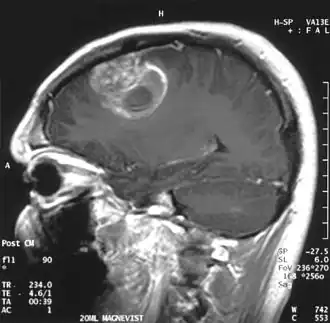

- Standardverfahren ist die Magnetresonanztomographie (MRT), auch Kernspintomographie genannt, ein diagnostisches Schnittbildverfahren zur Darstellung von Organen und Geweben mit Hilfe von Magnetfeldern. Sie basiert auf der Gewebestruktur und dem Wassergehalt und hat eine sehr hohe Erkennungsrate für Hirntumoren, ohne ionisierende Strahlung einzusetzen. Kontrastmittel ist nicht immer erforderlich. Die Magnetresonanzspektroskopie (MRS) ist ein in spezialisierten Zentren verfügbares Zusatzverfahren, um aus tumorverdächtigen Arealen ein Signalspektrum aufzunehmen und damit ihre chemische Zusammensetzung abzuschätzen.

- Die Computertomographie (CT) ist das Standardverfahren, wenn die MRT kontraindiziert oder nicht verfügbar ist. Sie ist schnell und auch nachts und an schwerkranken Patienten durchführbar. Sie hat jedoch etwas schlechtere Erkennungsraten und benötigt ionisierende Strahlung sowie meistens auch Kontrastmittel.